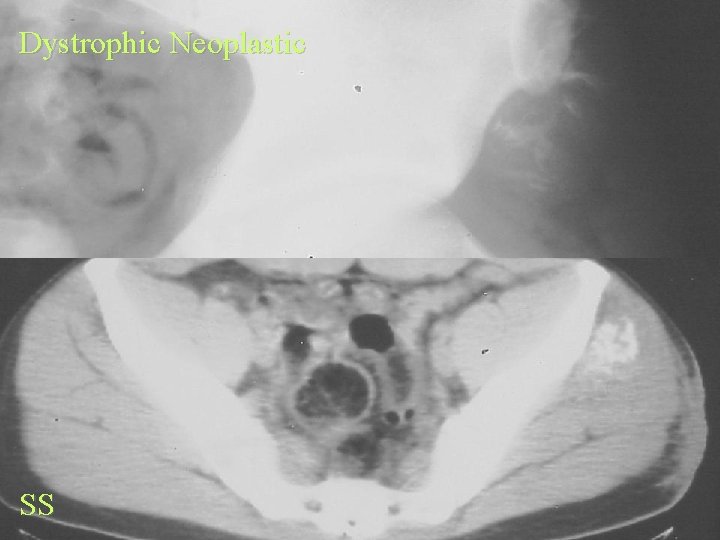

Soft Tissue Calcification By Cause Dystrophic Calcification • Neoplastic • Trauma • Inflammatory

Soft Tissue Calcification By Cause Dystrophic Calcification Neoplastic • Synovial sarcoma • Liposarcoma • Any less commonly

Dystrophic Neoplastic SS